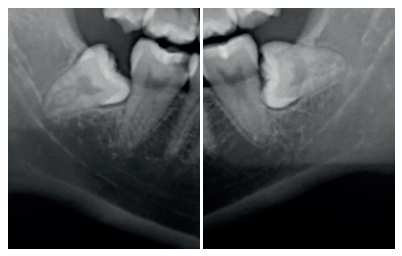

En la exploración radiográfica mediante radiografía panorámica se apreciaron ambos terceros molares inferiores retenidos, en una posición horizontal el 3.8 y mesioangular el 4.8 (Figura 1).